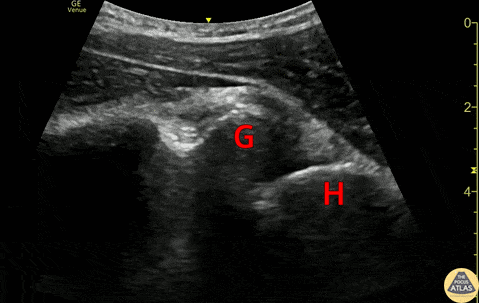

20s M with history of recurrent shoulder dislocations presented with pain and a deformity after being transferred from an urgent care after multiple failed attempts at closed reduction. POCUS confirmed dislocation at the bedside. The clip shown here is a posterior view of glenohumeral joint, illustrating the anterior displacement of the humeral head (H) in relation to the glenoid rim (G). A humeral head which is more than 1 to 1.5 cm anterior to the glenoid rim should be concerning for anterior dislocation (PMID 32111508). In this case, it is easy to see that the humeral head is almost 2cm anterior to the glenoid rim. After placement of an US guided interscalene nerve block, this patient was able to be reduced without difficulty. Dr. Anthony Rodriguez, PGY1 Denver Health Residency in Emergency Medicine Dr. Nimish Bhatt, Fellow Denver Health Ultrasound Fellowship